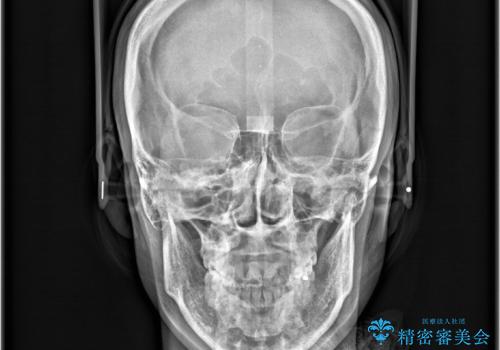

- 「歯のデコボコと前歯が出ているせいで口が閉じにくい」を主訴に来院された患者様です。

上下左右の4番(第一小臼歯)を抜歯をし審美ワイヤー装置で治療を行いました。

抜歯矯正により歯列のデコボコ(叢生)が改善し、前歯の突出も解消されたことで口元が下がり、すっきりとした印象となりました。